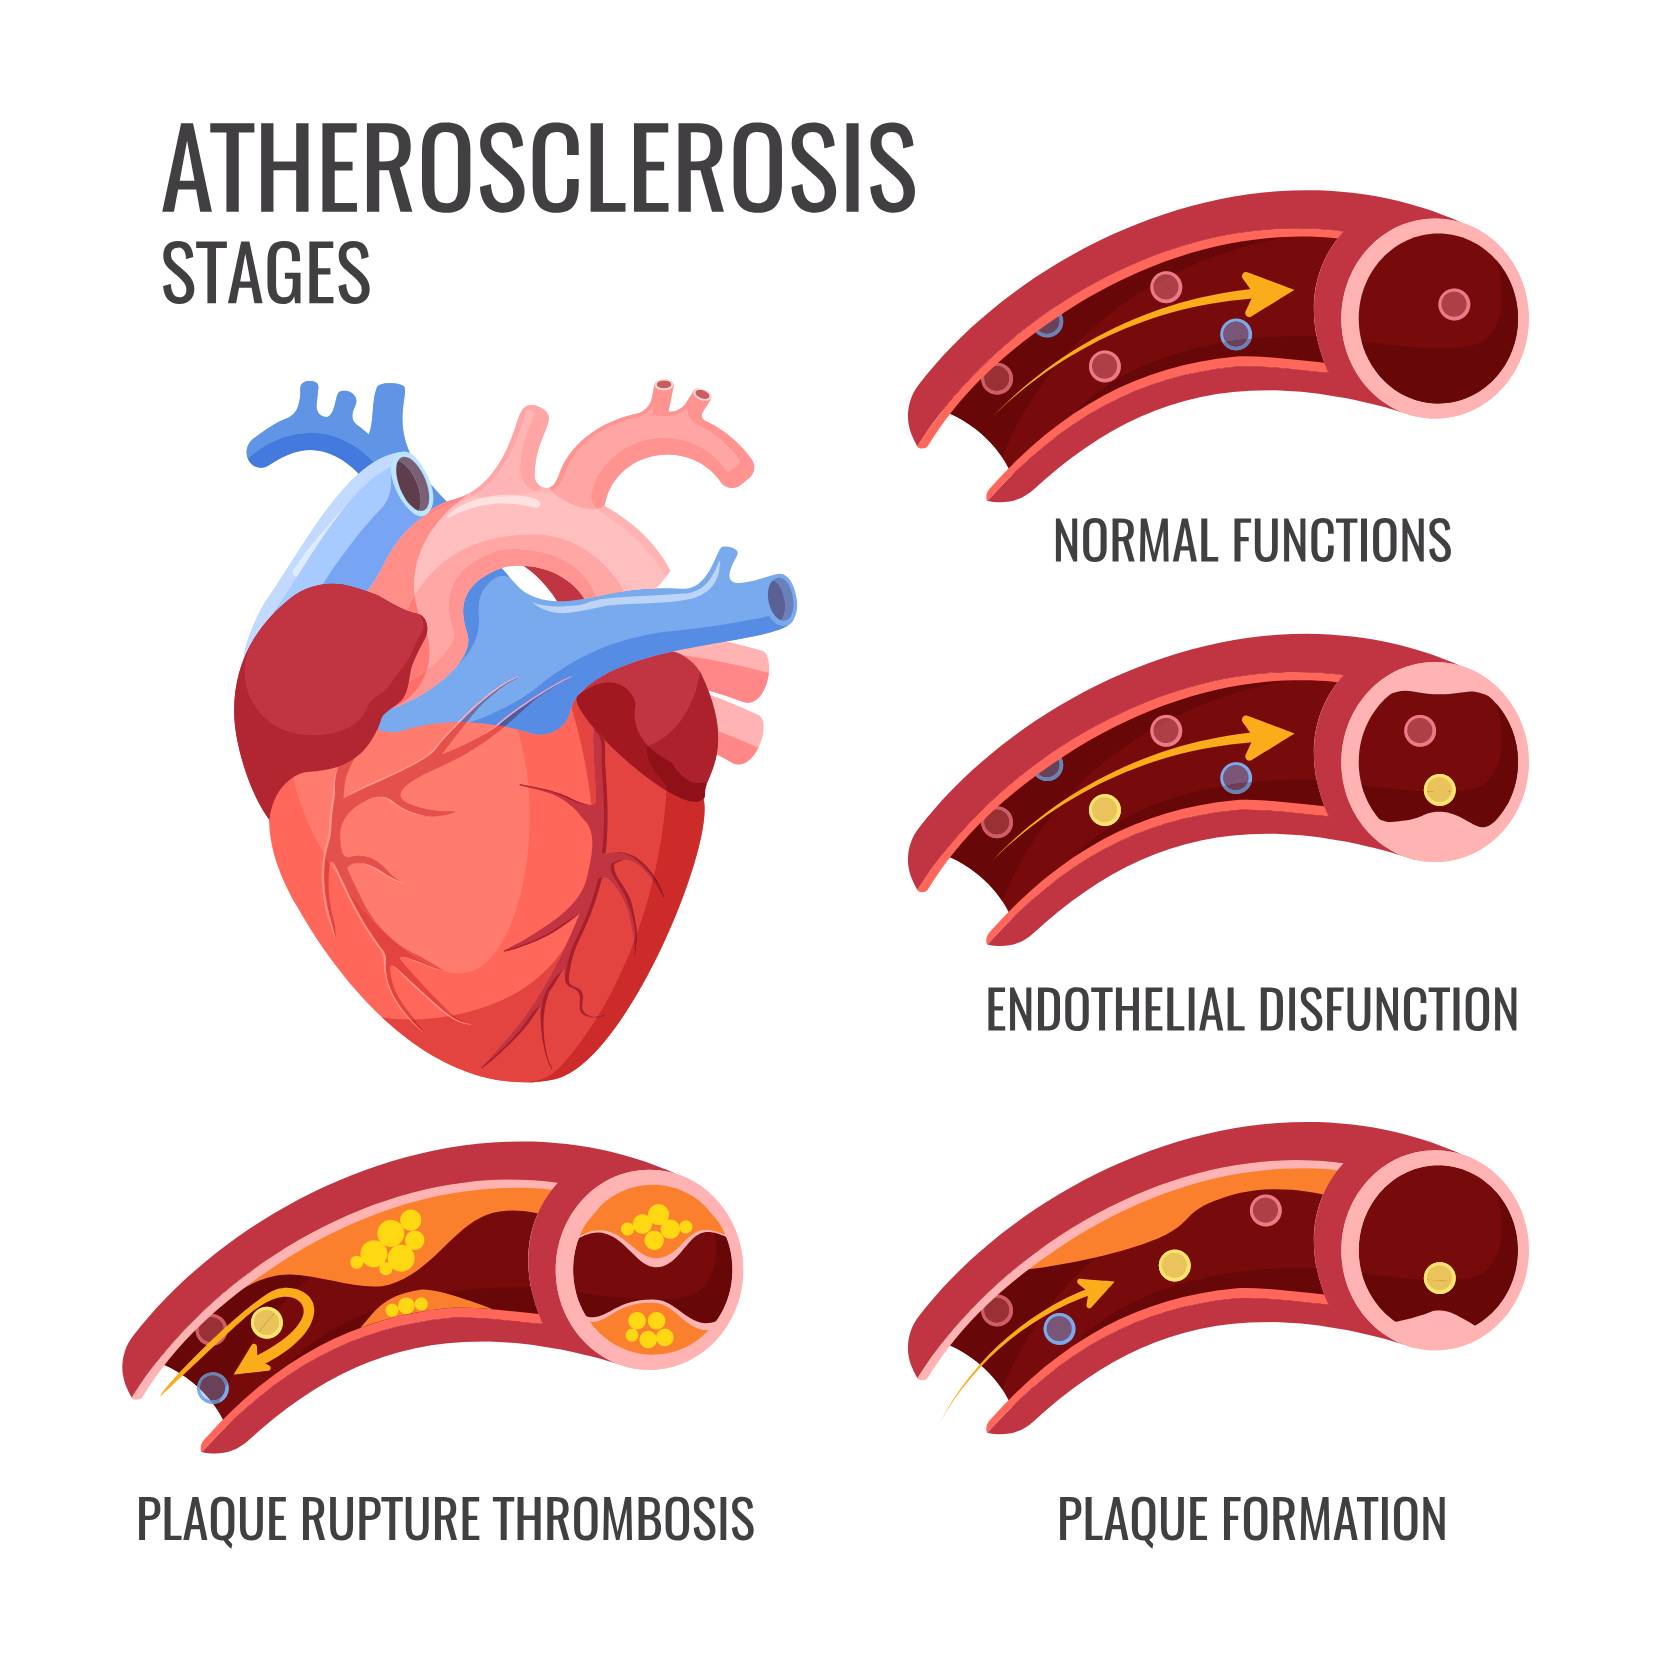

Carotid Artery Disease CAD

Carotid Artery Stenosis Wikidoc

The Warning Signs Of Clogged Arteries Heart Blockage Clogged

Carotid Artery Stenosis Wikidoc

Clogged Arteries Scientific Animations

Occluded Carotid Artery Carotisverengung Swiss Surgery